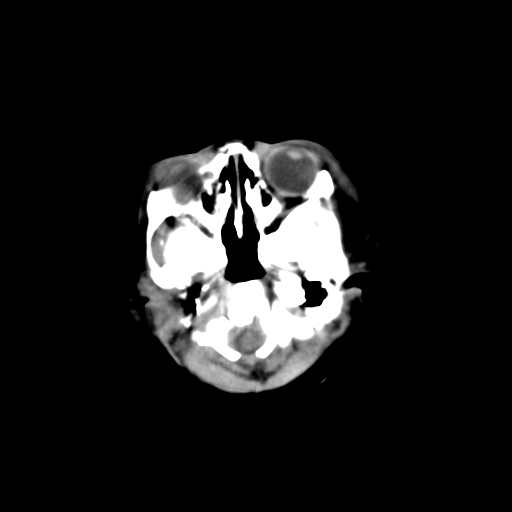

男,3天,患儿为剖腹产,生后嗜睡、拒乳。

1)考虑hie。2)sah?。3)右侧颞顶枕部及左侧颞顶部头皮血肿。

1、右侧颞顶枕部及左侧颞顶部头皮血肿。2、第五第六脑室。3、新生儿,脑白质密度还算可以,也无蛛血,不考虑hie。

脑室系统及脑沟裂闭塞,弥漫性脑密度减低,支持考虑hie,建议复查。右侧颞顶枕部及左侧颞顶部头皮血肿,另不除外胼胝体发育不良,复查